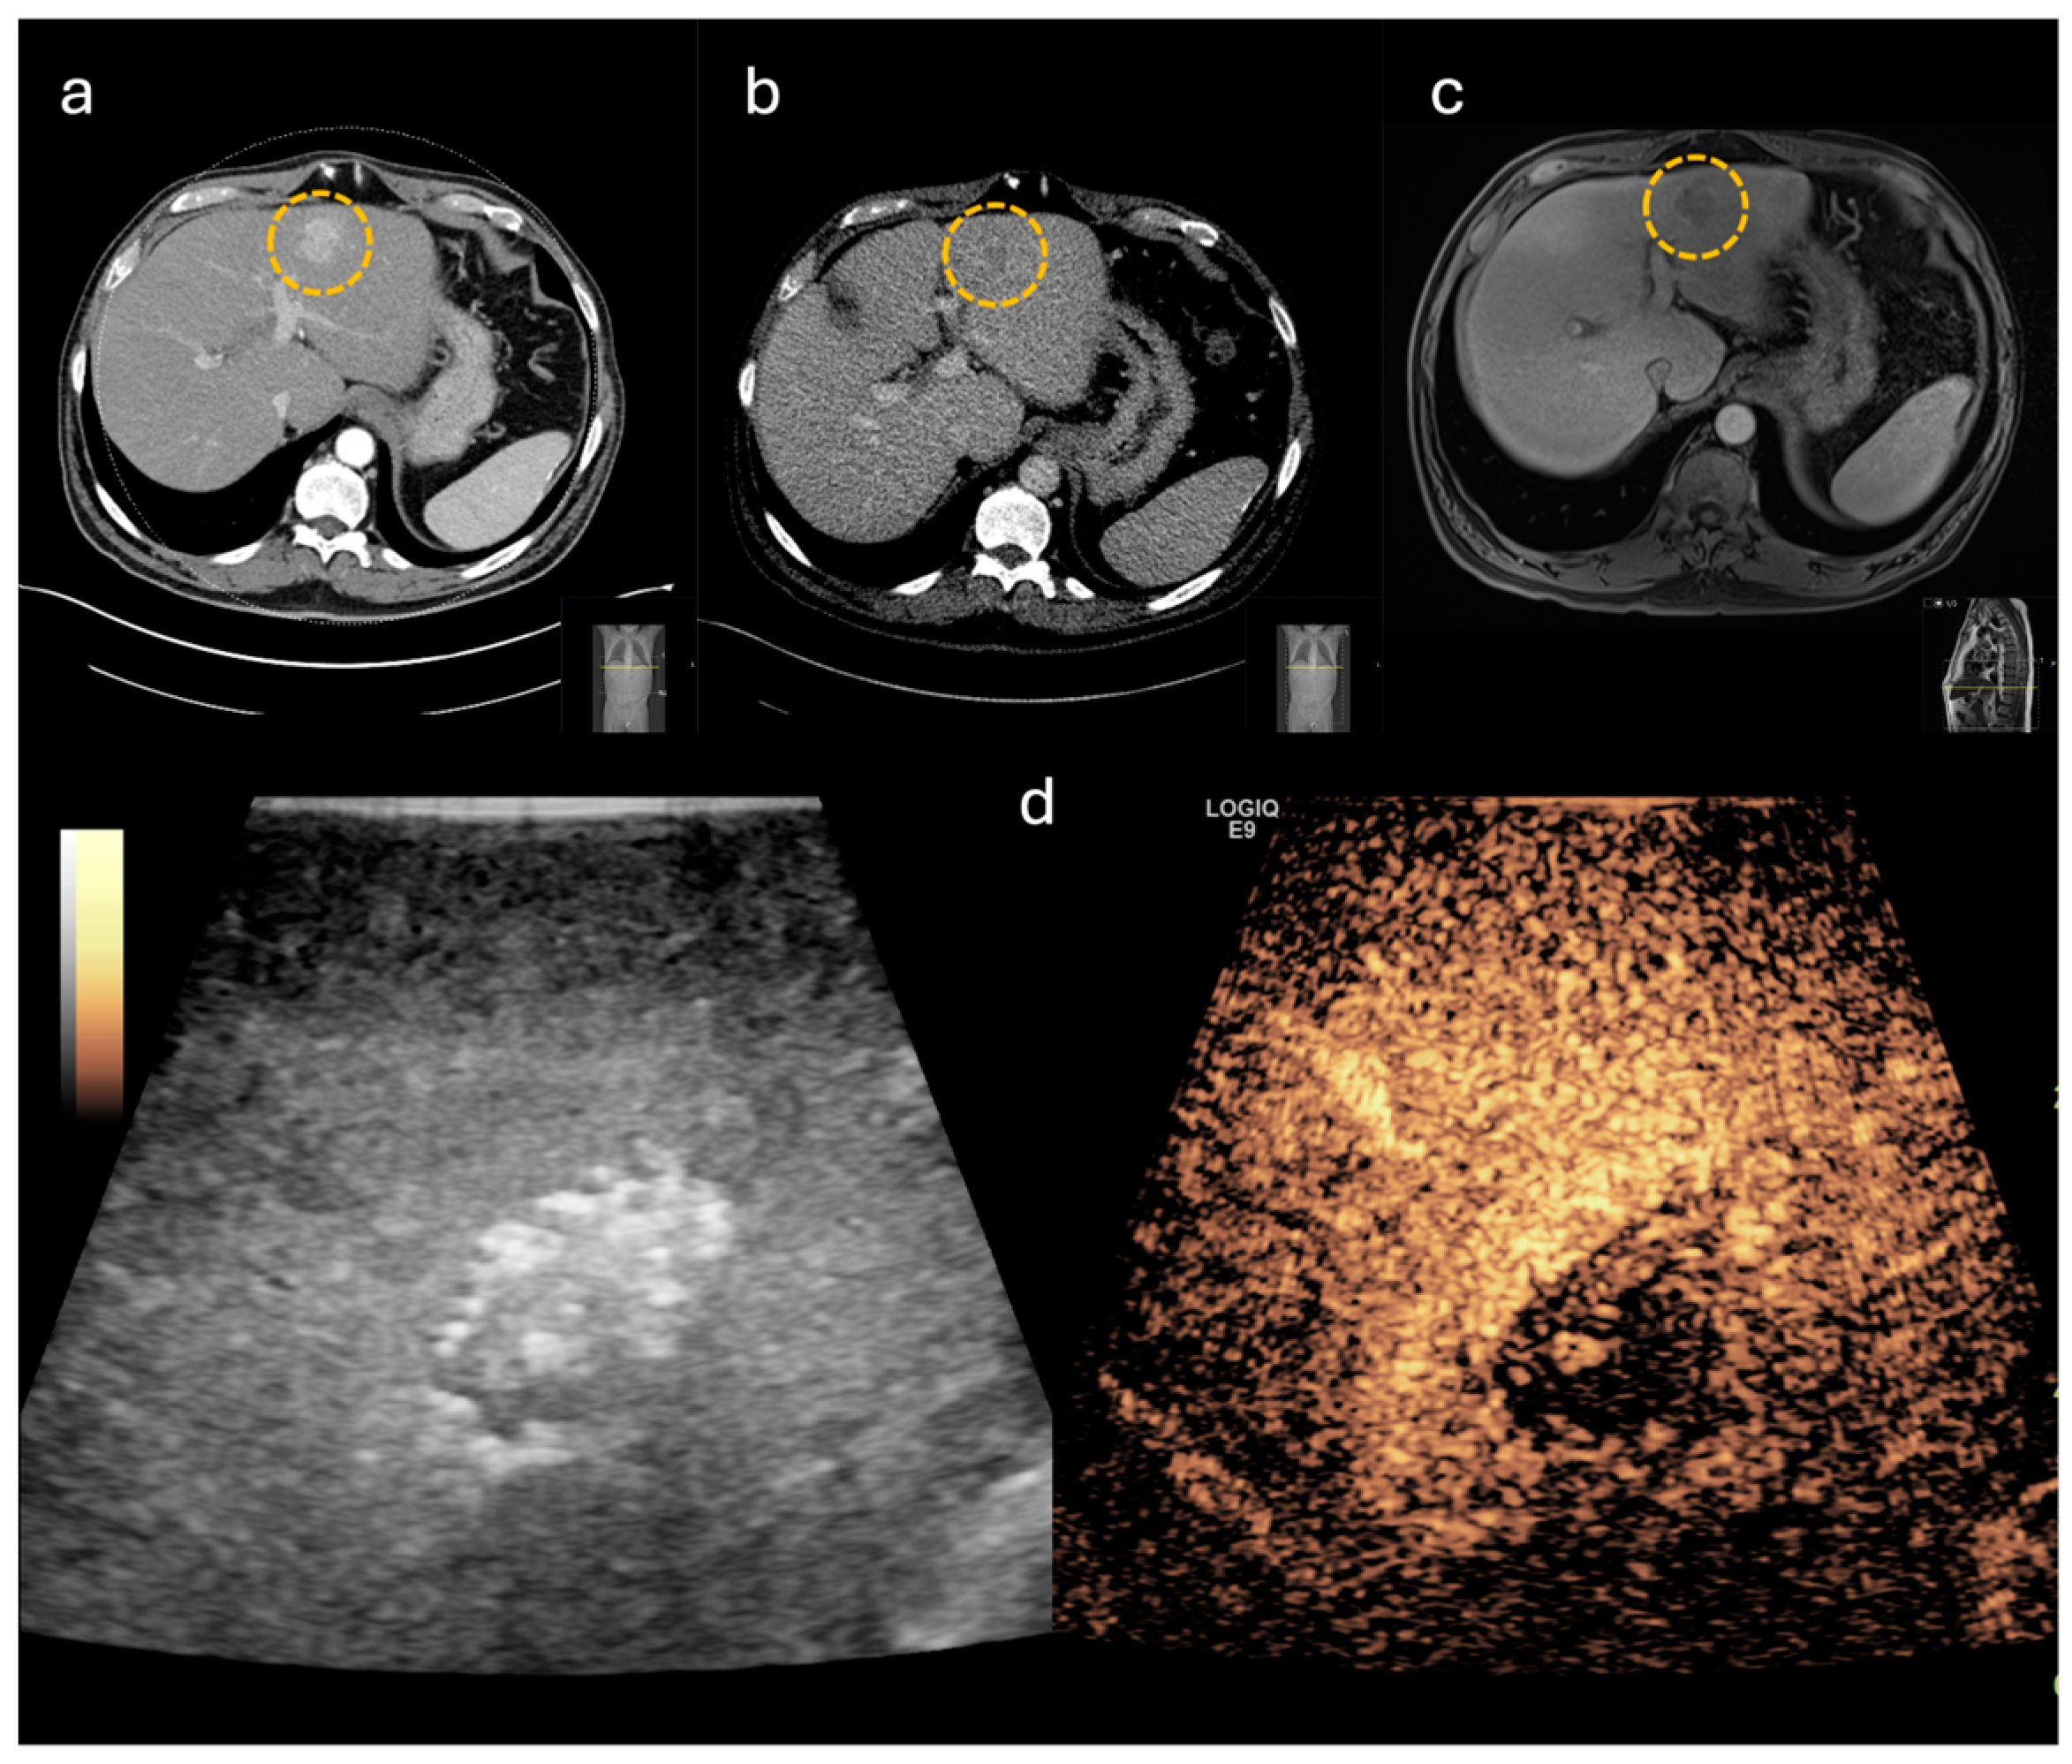

3.3. Accuracy of CE-IOUS